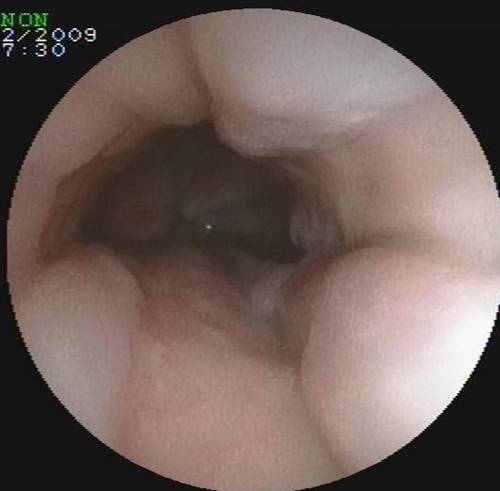

小肠镜检查:胆肠吻合口多发血管扩张,空肠吻合口息肉。

左侧为空肠空肠吻合口

胆肠吻合口迂曲的血管